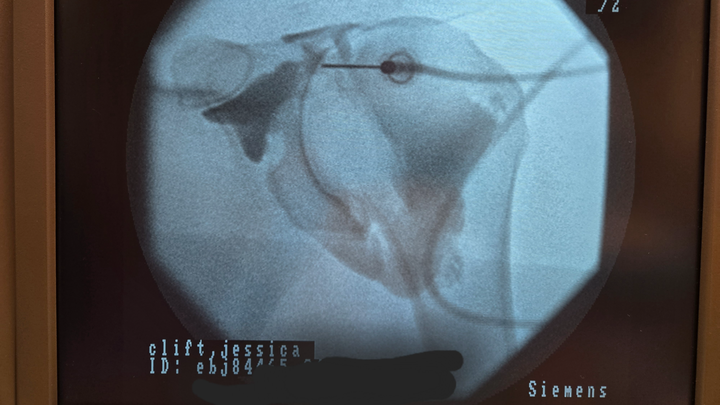

Here are the results from my MRI:

Musculature/Rotator Cuff: Partial thickness tear undersurface both supraspinatus and infraspinatus tendons, involving about 50% of the tendon thickness at the supraspinatus measuring about 1.3 cm from front to back and about 2.4 cm from side to side.

Infraspinatus shows similar high-grade partial-thickness tear involving about 75% of the tendon thickness, measuring 1.5 cm from front to back and 1.1 cm from side to side.

Subscapularis and teres minor attachments are normal. No muscular edema or fatty atrophy.

Impression:

1. Partial-thickness undersurface tear of both the supraspinatus and infraspinatus of the rotator cuff. This involves 50 and 75% of the tendon thickness.